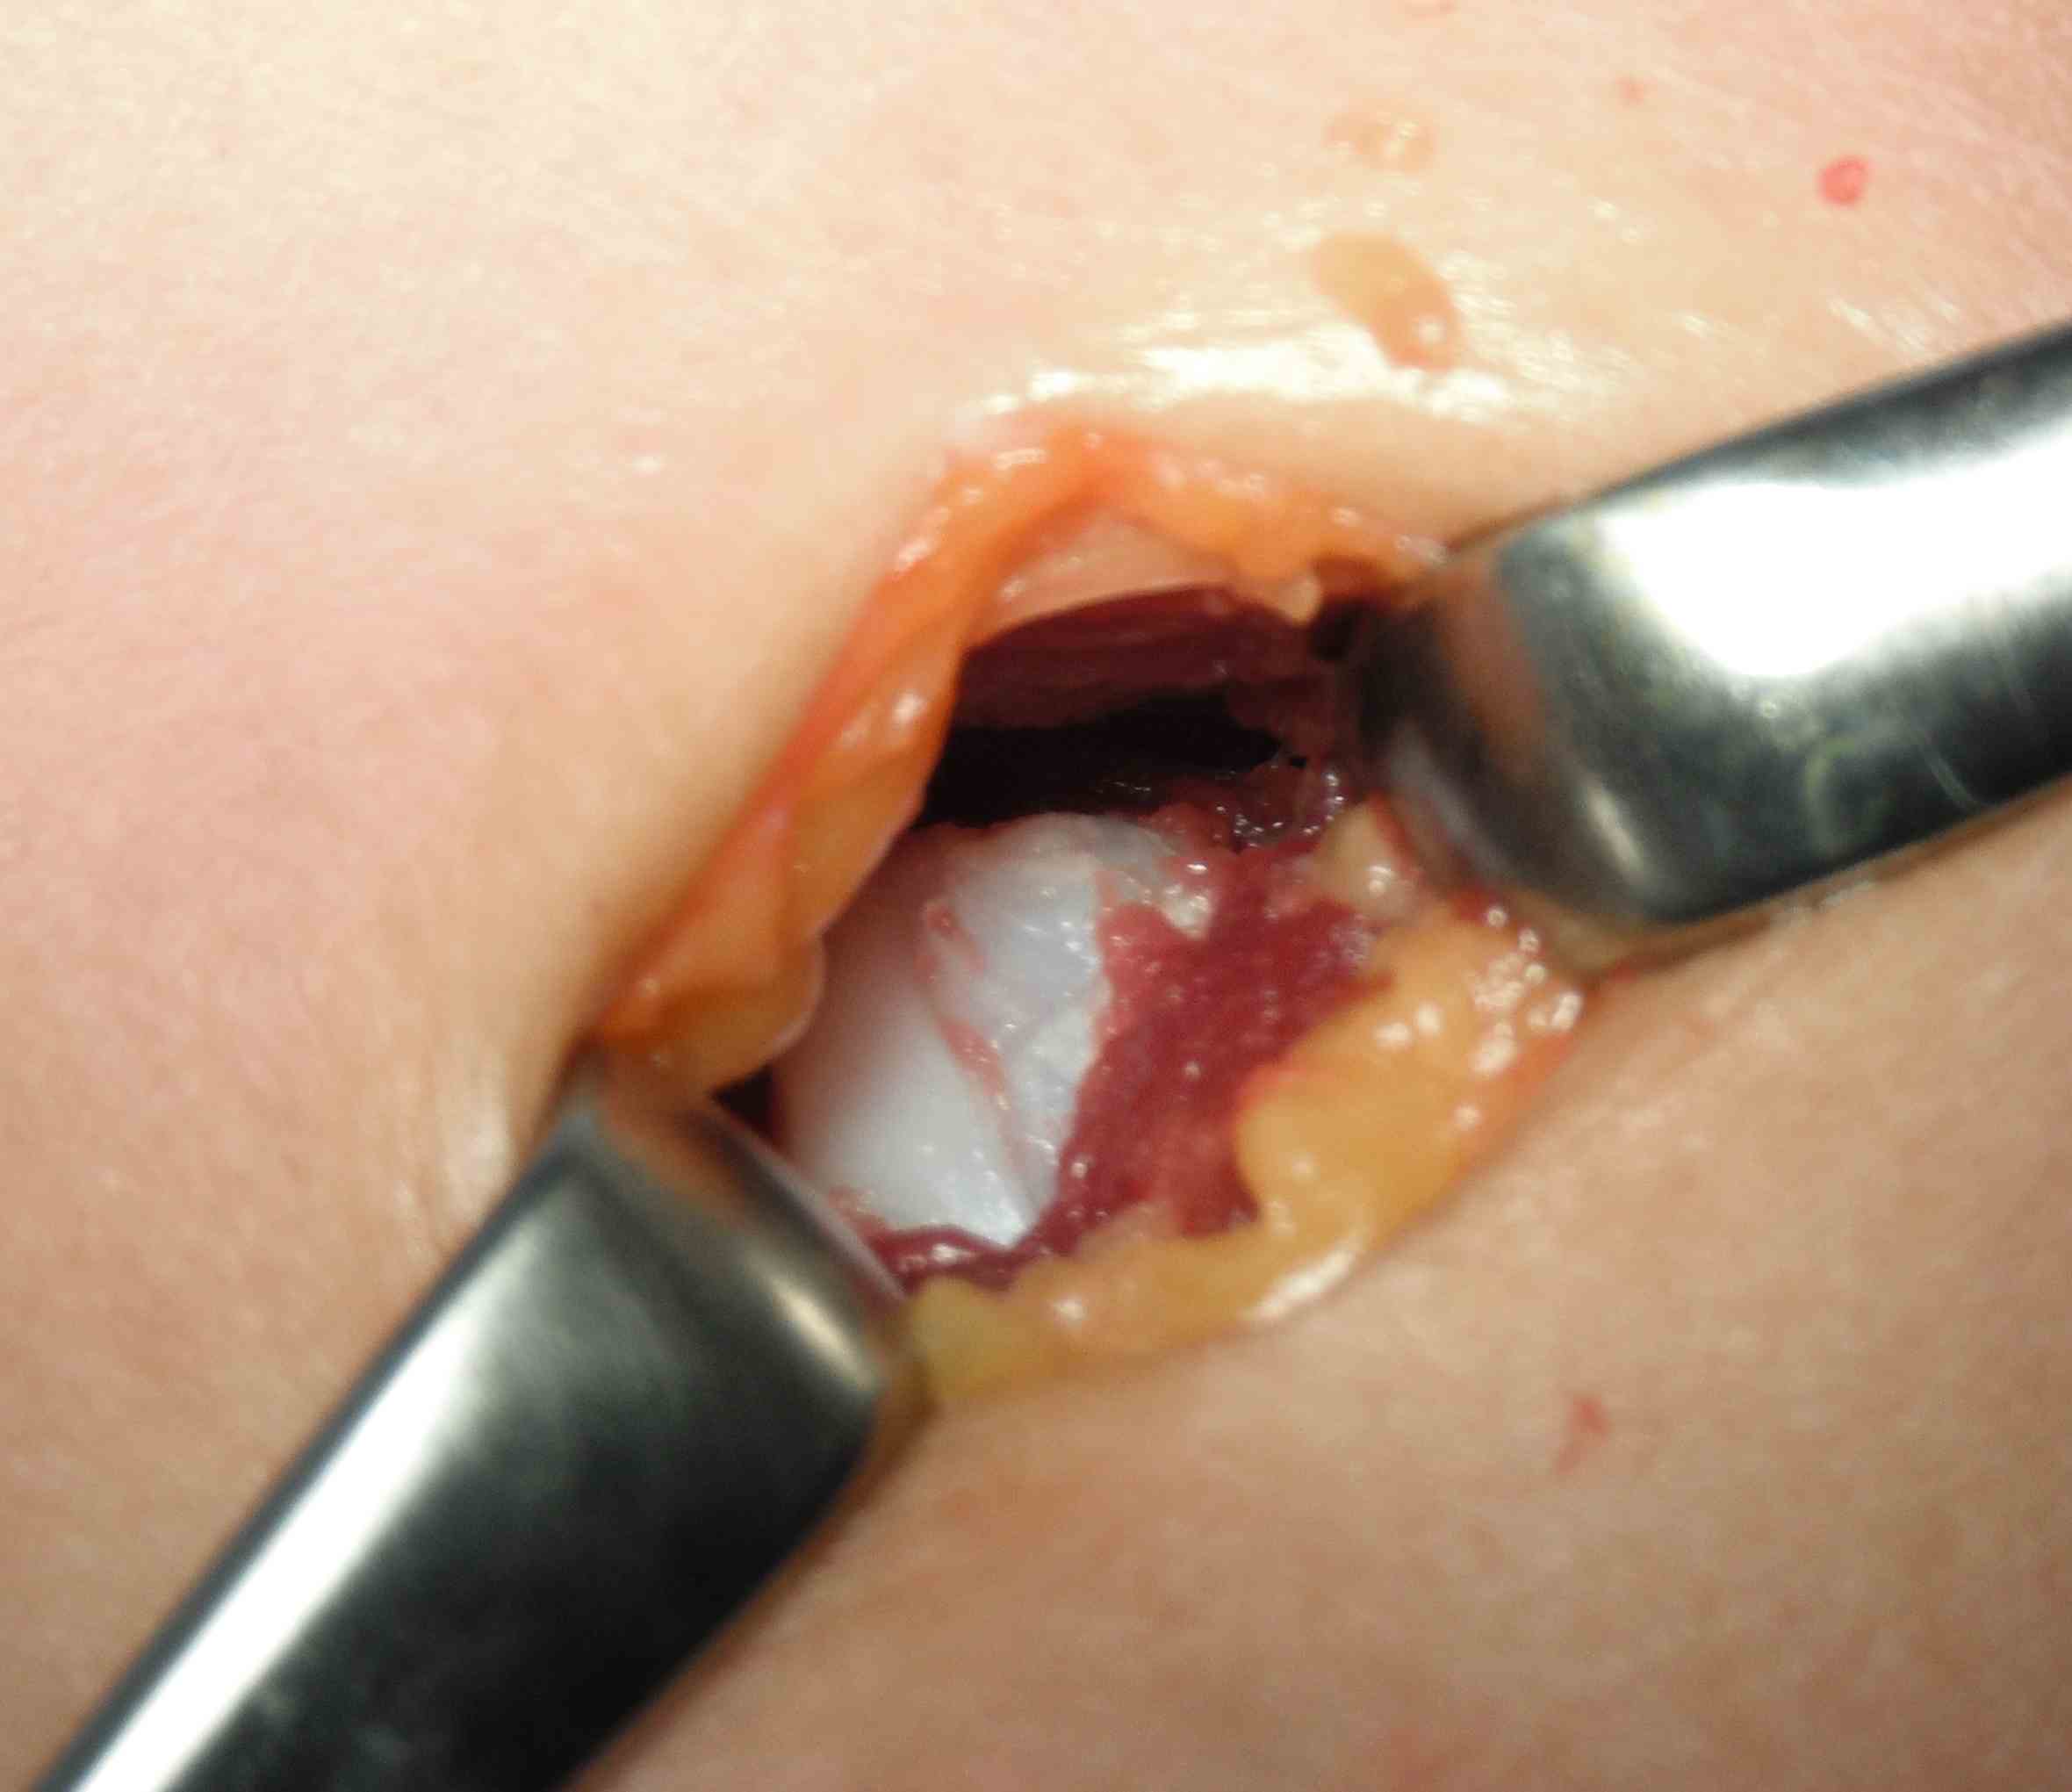

Pathology

Gross

- surface covered with irregular cartilage

- osteochondroma has cortical and medullary bone

Histology

- cap resembles disorganised physis

- irregular shaped underlying trabecular bone

- may contain calcified cartilage matrix